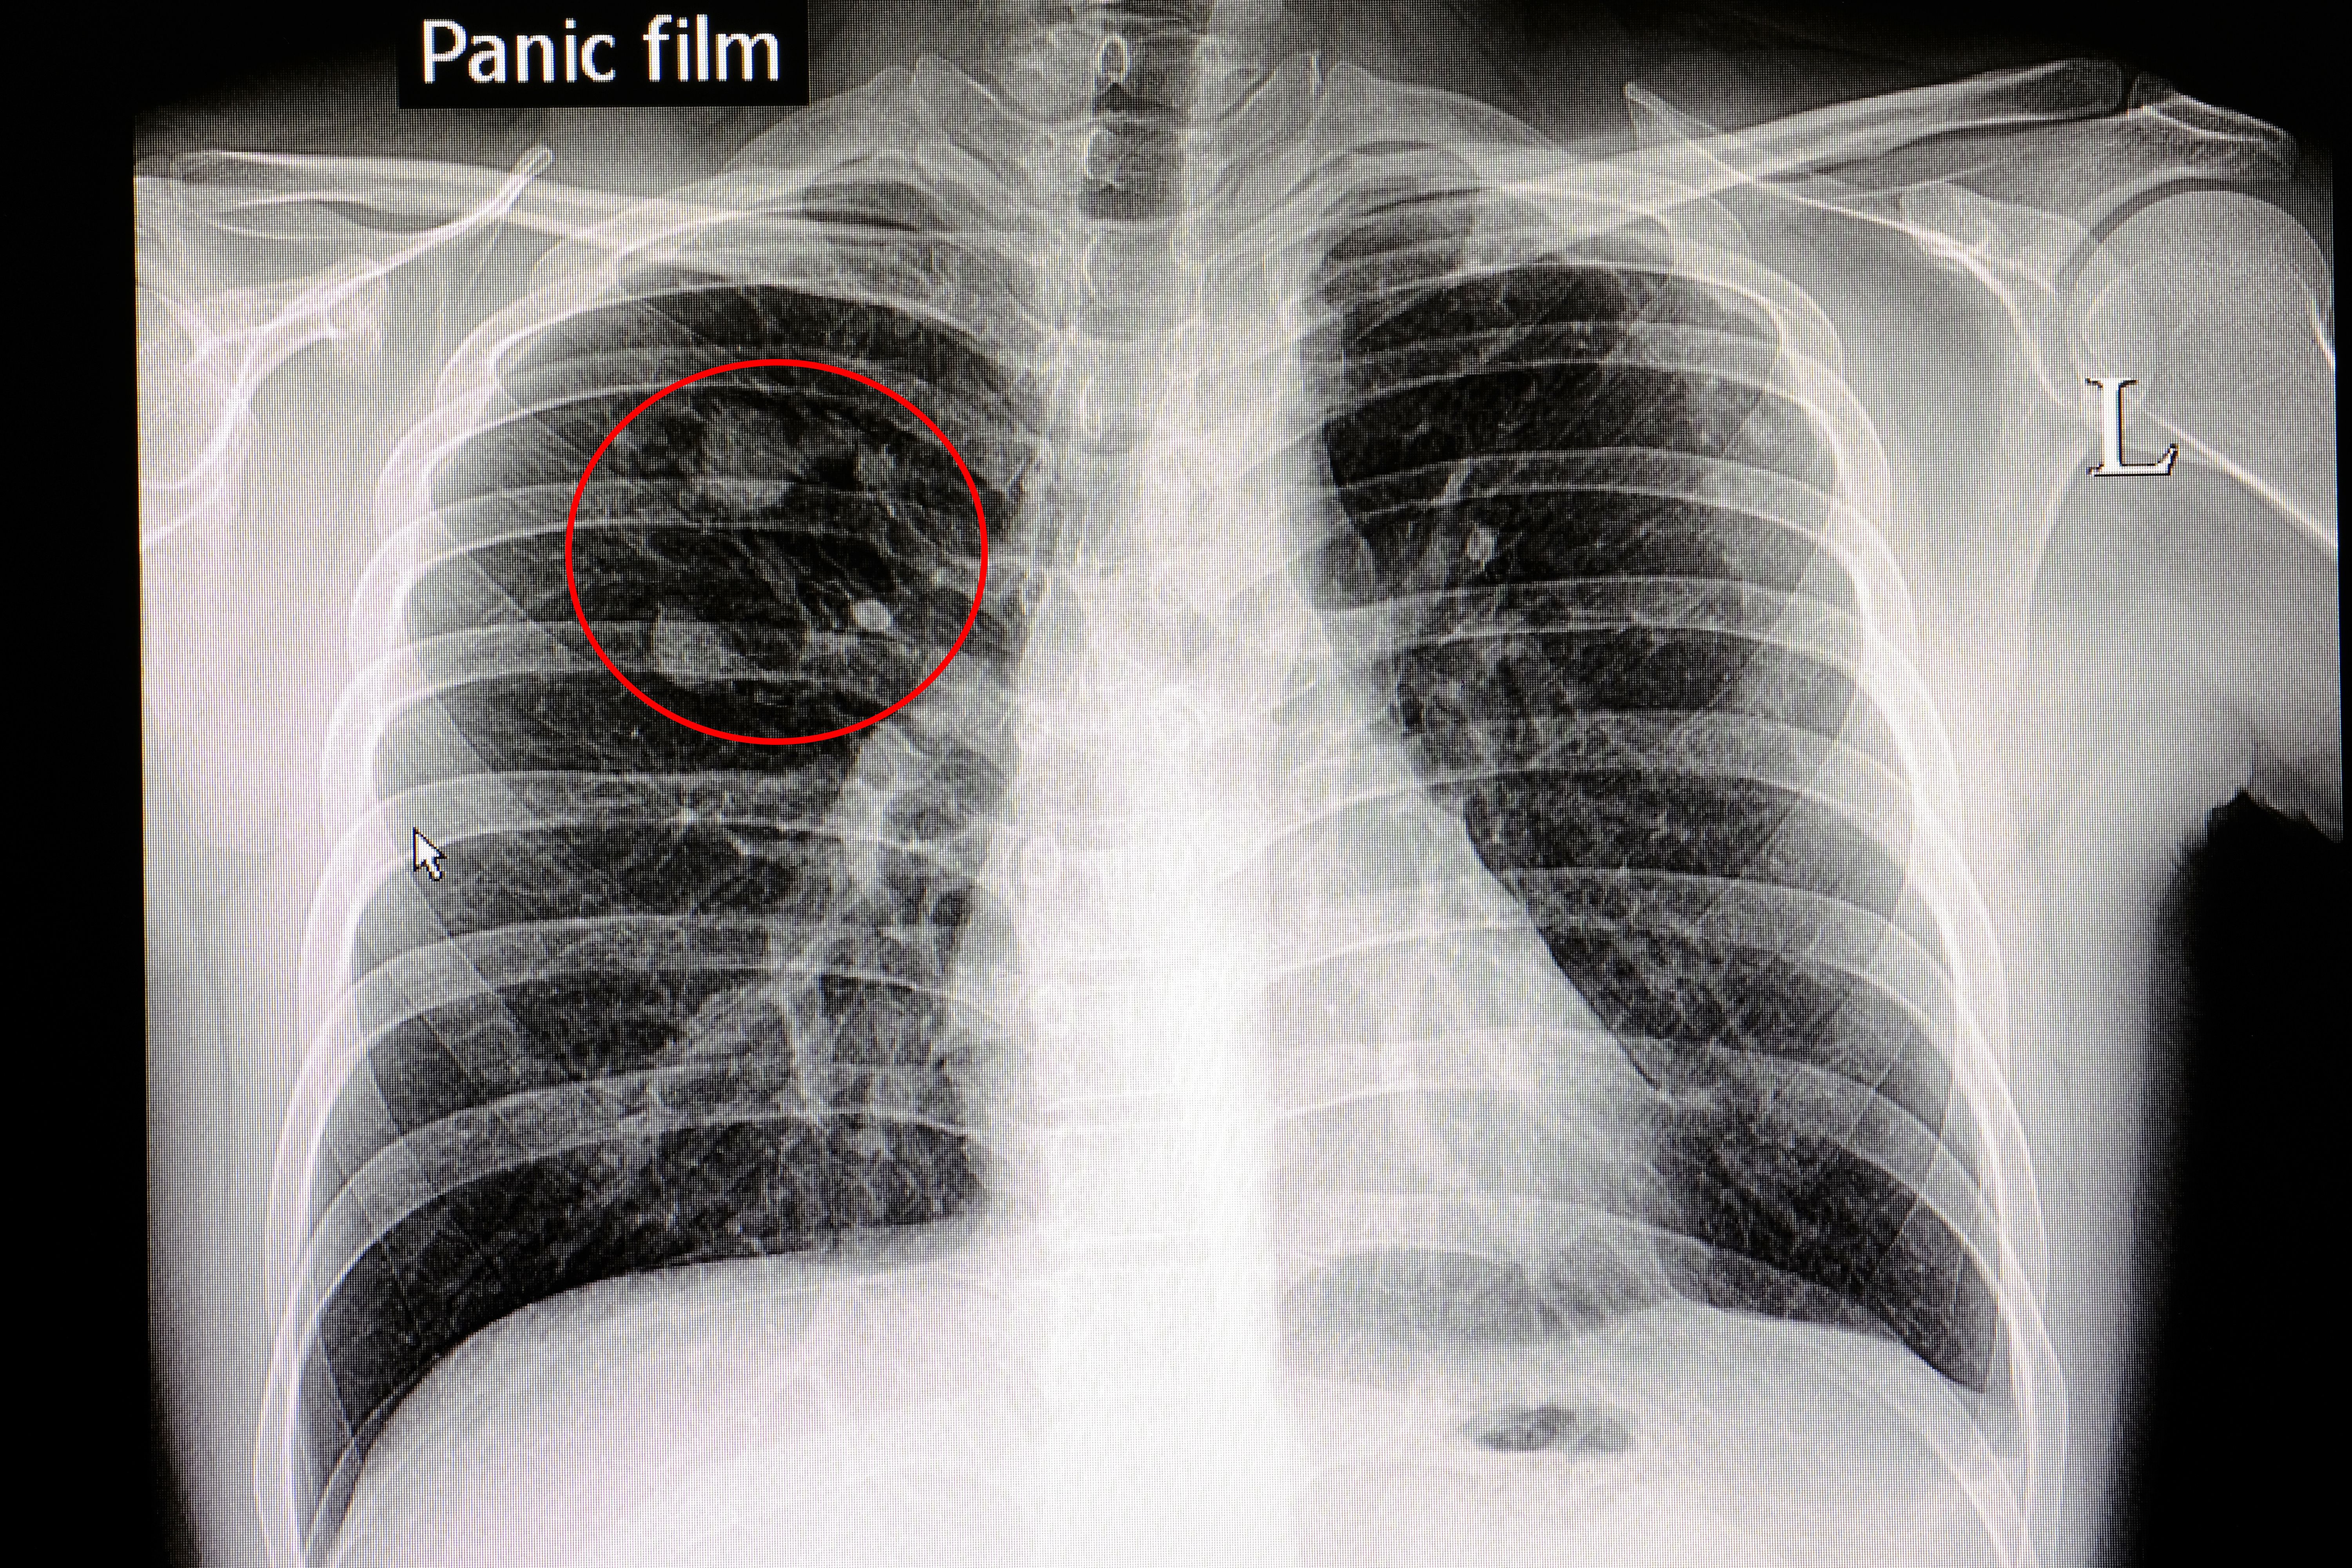

1. 胸部X線検査

最も一般的なスクリーニング検査です。健康診断でも広く用いられますが、早期の小さな病変は見逃される可能性があります。